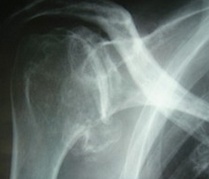

Luxation gléno humérale

- la luxation de l'épaule est une perte de la relation entre les surfaces articulaires de l'humérus et de la glène de l'omoplate (scapula), elles sont fréquentes